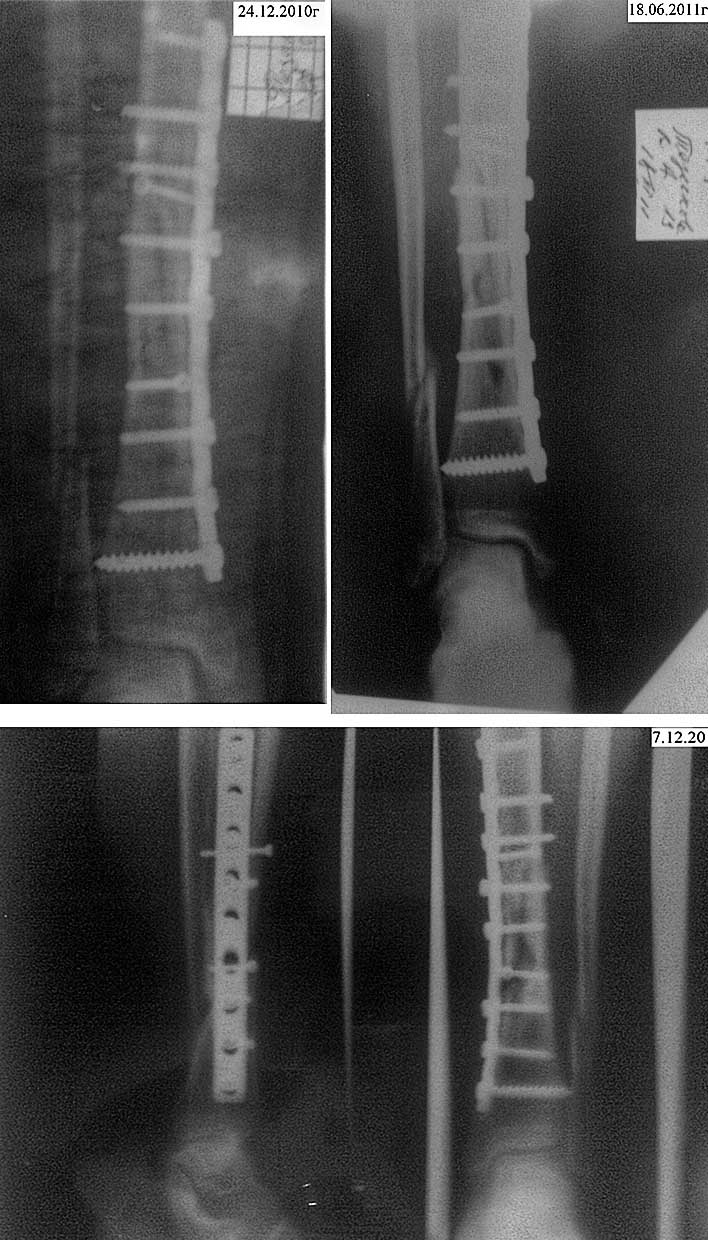

Пациент девушка, 1992 г.р. 11 декабря 2010 годав результате ДТП имеемперелом средней нижней правой третьей большой берцовой кости.

операцию сделали 15 декабря 2010, собрали, поставили пластину.Периодические снимки приложены:24.12.2010 - сразу после операции18.06.2011 - промежут. снимок7.12.2011 - последний снимок.Сейчас диагноз звучит так:Диагноз- сросшийся перелом средней нижней правой третьей большой берцовой кости с наличием пластиныХромота, опираться на ногу невозможно,Ходить запрещают, предлагают ждать еще 2 месяца.Есть мнение, что перелом не сросся(?).Просьба прокомментировать адекватность произведенного вмешательства и перспективы,лечение.Вероятно требуется повторное вмешательство.

Здесь очевидное несращение. В перспективе - разрушение имплантата. Надо делать повторную операцию. Мы бы дообследовали в отношении вялотекущей инфекции, малоинвазивно убрали пластину (посев при удалении) и сделали бы закрытый интрамедулярный остеосинтез (который бы изначально выбрали бы, если бы пациентка лечилась у нас) . Возможно, стоит использовать гвоздь с антибактериальным покрытием.